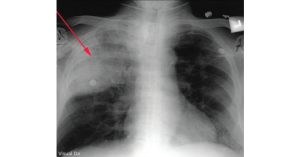

• Visual Dx Answer: a) Acute Chest Syndrome